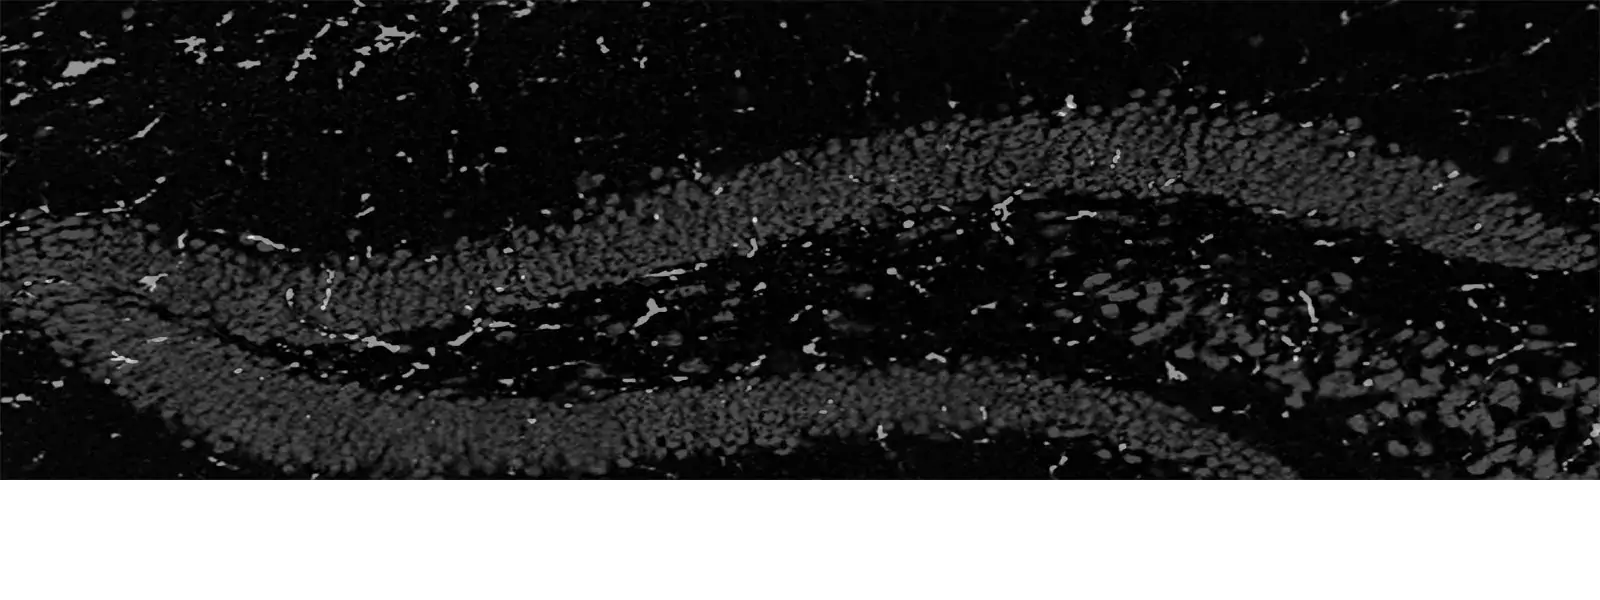

hippocampus

Vi bedriver experimentell och klinisk forskning om Alzheimers sjukdom och andra neurodegenerativa sjukdomar. Vårt mål är att förstå sjukdomsorsakerna och att ta fram nya behandlingar.